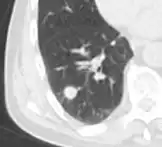

- Pleural retraction is far more common in cancers.[9] It is the pulling of visceral pleura towards the nodule.[9]

-

Nodule with pleural retraction.[9] -

In this case, pleural retraction is seen as a triangular fat component.[9]